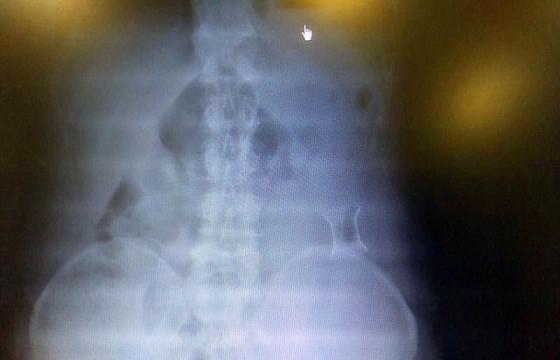

受試患者在結腸端端吻合術中,使用我司新研制產(chǎn)品達到了理想的預期效果。患者術后7天、14天X光片顯影,可降解腸道支架均能按研制設計的預期時間節(jié)點保持應有強度,術后21天X光片顯示可降解腸道支架已完全破碎,并排出體外。在整個試驗過程中,病患無任何不良反映,耐受良好。